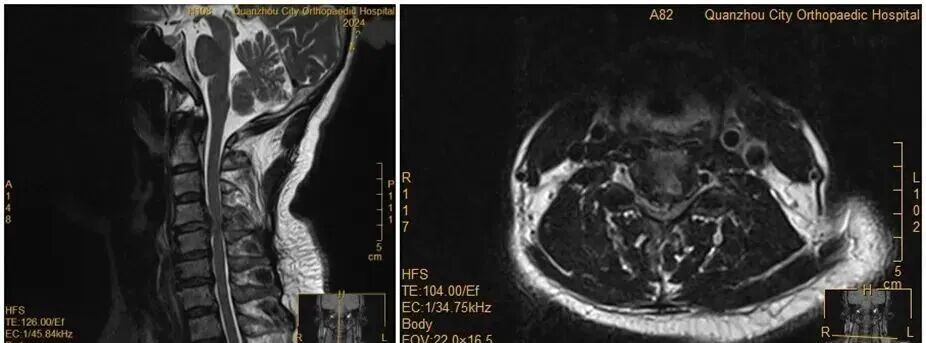

此前,她因手麻、酸痛到医院就诊,被查出颈椎间盘突出症。主治医师回忆:“会诊时我们明确告知患者,她的颈椎间盘已经巨大脱出,符合手术指征,建议尽快手术。但她坚持想保守治疗。”

没想到,会诊当晚,王女士翻身拿手机的瞬间,双手突然失去知觉——关键肌肌力降至1级或0级,确诊为瘫痪。“推测是翻身时,脱出的椎间盘突然进一步卡压到脊髓神经,引发了急性症状。”医生表示。

王女士术前MRI

虽然已经出现了瘫痪,王女士仍然惧怕手术,不愿意接受手术。经过医务团队及王女士家人耐心解释及劝解后,王女士才愿意接受手术治疗。医院为王女士紧急实施手术。手术顺利,经过一段时间恢复,她的肢体功能逐渐回归正常。